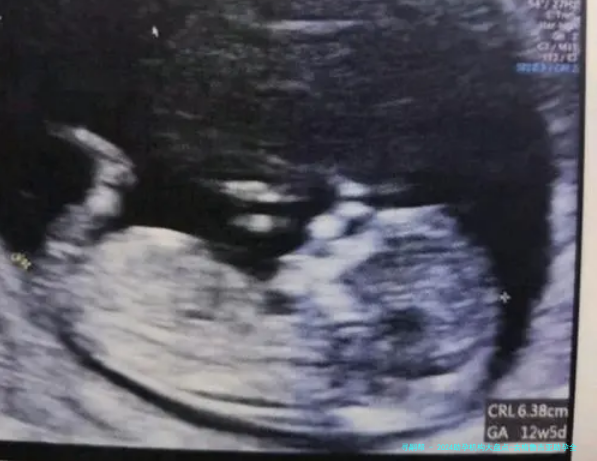

| 在格鲁吉亚医疗与待产阶段(约6-12个月) | 完成医疗步骤(促排卵、取卵/取精、胚胎培养与移植)、通过医疗学形式认定妊娠成功、孕期观测。 | 医疗流程需遵照医生的一对一引导;建议留存备用应急资金以应对可能的额外医疗花费。 |

| 孕期监测与管理 | 定期产检、营养与心理支持 | 选择提供全程孕期监测与管理的服务套餐 | 通常包含在总费用或保险中 | 整个孕期 | 持续、专业的孕期管理是成功的重要一环 |